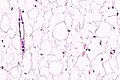

Mature adipose tissue (lipoma). H&E stain.

• Collection of mature adipocytes.

• Microscopically not definitely distinguishable from mature clump of fat.

The sections show mature adipocytes. There is no increase in vascularity. No thick fibrous septa are present.